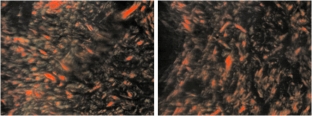

According to the results of the study, an excess of type 3 collagen, which has weak strength properties, was found in a large number of the studied patients, which indicates a congenital pathology of the connective tissue. The ratio of type 1 collagen to type 3 collagen in these patients was 3.68, while the ratio of the two types of collagen in the control group was 4.18. Visually, the decrease in the ratio of type 1 collagen to type 3 looked like an increase in green-colored areas, which were type 3 collagen fibers. At the same time, collagen fibers of the 3rd type had different diameters and formed a parallel fibrous network.